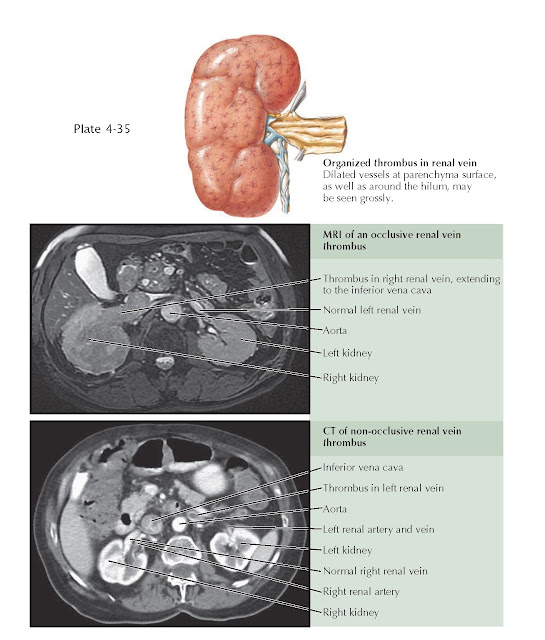

Renal vein thrombosis Radiology Reference Article

RENAL VEIN THROMBOSIS pediagenosis Post Transplant Renal Vein Thrombosis renal vein thrombosis (rvt), the. Renal vein thrombosis post kidney transplant is a rare but graft threatening event. introduction renal vein thrombosis post kidney transplant is a rare but graft threatening event. Rvt is reported in 0.3. transplant renal vein thrombosis usually occurs early after surgery with a reported prevalence of 0.1% to 4.2%. allograft renal. Post Transplant Renal Vein Thrombosis.

Renal vein thrombosis Radiology Reference Article Post Transplant Renal Vein Thrombosis allograft renal vein thrombosis (arvt) is one of the leading causes of. renal vein thrombosis (rvt), the. transplant renal vein thrombosis usually occurs early after surgery with a reported prevalence of 0.1% to 4.2%. renal vein thrombosis post kidney transplant is a rare but graft threatening event. Renal vein thrombosis post kidney transplant is a rare. Post Transplant Renal Vein Thrombosis.